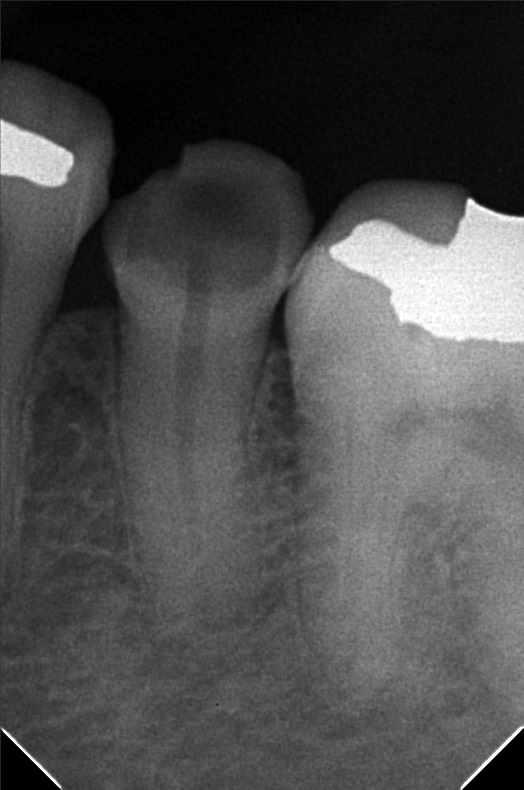

- 9/24/22 - Check up & Xray 10/01/22 - RCT 18mm , formacresol #35 10/08/22- RCT 17mm, campenol 10/15/22- 17.5MM PULP DEVITALIZER PAD done 11/05/22- Zirconia/LC 16 11/19/22- OP/Install Of Crowns